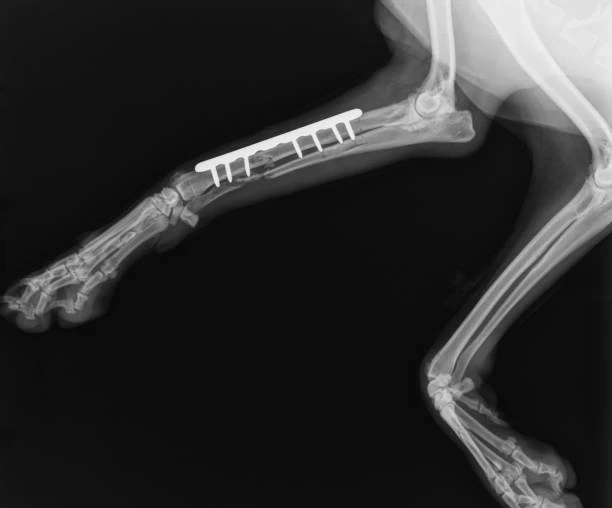

O raio x em cães é um procedimento seguro e indolor para os pets, permitindo que os veterinários visualizem estruturas ósseas e órgãos internos com detalhes, auxiliando no diagnóstico de uma ampla gama de condições de saúde. Com equipamentos modernos e uma equipe especializada, nossa clínica veterinária em Paulínia realiza exames de imagem com precisão e agilidade, contribuindo para um tratamento eficaz e personalizado para cada animal.

• Identificação de fraturas e lesões ósseas;

• Auxílio no acompanhamento de tratamentos ortopédicos;